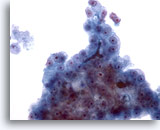

画像 5

肝FNA – 良性胆管細胞

良性胆管細胞の集塊。蜂巣状に配列し、均一な小型の核がみられます。

20倍

画像 5

肝FNA – 良性胆管細胞

良性胆管細胞の集塊。蜂巣状に配列し、均一な小型の核がみられます。

20倍